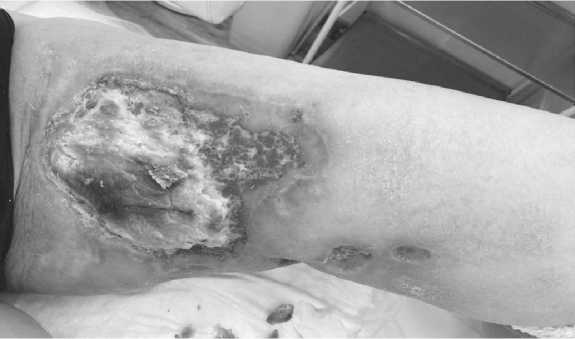

С 13.04.23. В течение месяца проведено сдержи вающее лечение по программе « РЕР - С ». Все препа раты принимались перорально в стандартных дозах ( этопозид 50 мг / сутки , преднизолон 20 мг / сут , ци - клофосфан 50 мг / сут , прокарбазин 50 мг / сут ). Еже недельно проводился клинический анализ крови с коррекцией доз по необходимости . Вопреки химио терапии заболевание продолжало прогрессировать ( Рисунок 1). Принято решение о проведении палли ативного курса лучевой терапии .

Рисунок 1. Поражение кожи внутренней поверхности левого бедра. Определяется выраженный отек мягких тканей левого бедра с наличием множественных разнокалиберных участков изъявления кожи и зонами некроза. Края дефектов обработаны раствором бриллиантового зелёного.